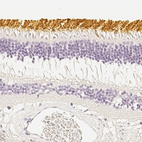

Immunohistochemical staining of human eye, retina, kidney, liver and lymphoid tissues using Anti-OPN1SW antibody HPA013562 (A) shows similar protein distribution across tissues to independent antibody HPA014083 (B).